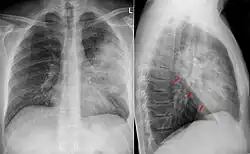

Röntgen

Beim Verdacht auf eine Pneumonie werden in der Regel zwei Röntgenbilder der Lunge angefertigt. Im Röntgenbild stellen sich schlecht belüftete Areale hell dar. Diese können z. B. auf eine Lungenentzündung hindeuten. Diese Veränderung (Infiltrat) entsteht durch die Einwanderung von Leukozyten (Infiltration) und die entzündlich bedingte Schwellung. Sind die luftleitenden Teile der Lunge und die Lungenbläschen nicht betroffen – wie bei einer interstitiellen Pneumonie (Entzündung des Bindegewebes zwischen den Lungenbläschen) –, stellen sie sich im Röntgenbild dar (positives Bronchopneumogramm). Sind hingegen die Lungenbläschen in dem entzündeten Bereich nicht mehr zu sehen, deutet dies darauf hin, dass sich dort Flüssigkeit befindet und die Entzündung in den Lungenbläschen stattfindet wie z. B. bei einer Lobärpneumonie.

Die Abgrenzung einer schweren Tracheobronchitis von einer Bronchopneumonie ist schwierig und teilweise erst im Verlauf möglich.